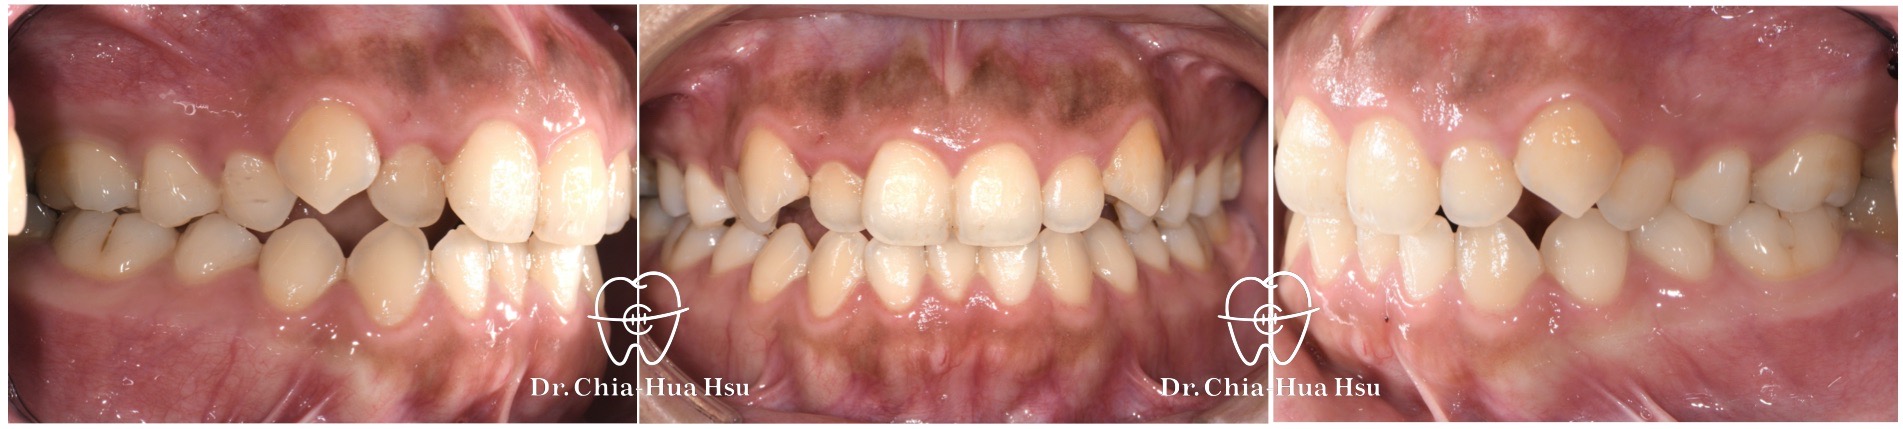

治療前

治療後